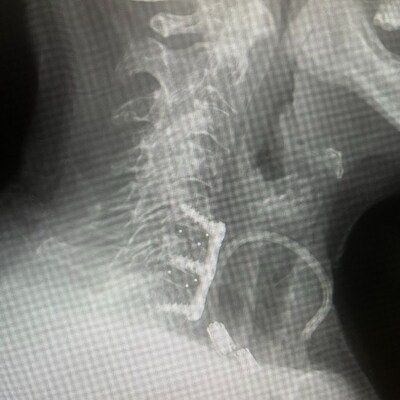

FLOWOOD, Miss., Feb. 11, 2026 /PRNewswire/ -- Zavation Medical Products, LLC ("Zavation"), announces the release of its most advanced cervical interbody implant to date—the integration of NanoPrime® Titanium Ion Bond Technology with the company's proprietary Labyrinth® porous PEEK architecture. This combination is engineered to elevate the mechanical advantages of PEEK with the biological benefits of titanium.

Combined, these technologies deliver an implant platform that maintains the imaging clarity and elastic modulus of PEEK while introducing an osteoconductive nano-surface intended to promote early cell attachment, induce hydrophilic wicking, and reduce stress shielding 4,5.

Derek Kuyper, the Chief Executive Officer of Zavation, shared his excitement, stating: The NanoPrime® Labyrinth® Cervical interbody represents the next step in strengthening our platform of interbody materials and structures, giving distributors and surgeons greater design and stiffness modalities. By integrating NanoPrime® and Labyrinth® technologies into our cervical line, we're offering a world first interbody cage with the macro, micro, and nano level features of 3D Titanium with the imaging characteristics and device stiffness of PEEK, the best of both in one device.